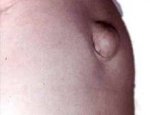

Лечение пупочной грыжи у взрослых Занятие спортом всегда считалось проявлением здорового образа жизни, ведь любой человек, который без вредных привычек занимается спортом будет здоровее всех остальных и проживет дольше. Но ведь некоторые виды спорта могут больше навредить, чем помочь в улучшении здоровья. Возьмем те же приседания со штангой точно угадать нужное напряжение практически нереально. Штанга будет или слишком легкая для спортсмена и он не будет ощущать нагрузки либо будет слишком тяжелая и он просто порвет связки или потянет спину. Это очень больно, так как ходить потом неудобно и заживает потянутая спина долго. Да и потянутая спина это не самая большая проблема, которая может постигнуть как молодых спортсменов так и более старших мужчин. При больших нагрузках есть шанс получить грыжу пупка или паха, а это уже на много хуже потянутой спины.Проблема в том, что у молодого спортсмена грыжа заживет на много быстрее, чем у взрослого мужчины и в таком возрасте получить травму практически считается выбыванием из спорта как такового. Лечение пупочной грыжи у взрослых это очень длительный процесс и отнимает много сил, нервов и денег, а после такого рода травмы идти заново и поднимать штангу никто не захочет. Да и после грыжи шансы опять получить травму такого типа повышаются в несколько раз область лета уже потянута и удержать ее в нормальной форме можно только если не делать никаких тяжелых упражнений. Так что если Вы решили идти на тяжелую атлетику или просто в качалку потаскать штангу всегда делайте все упражнения с головой и не пытайтесь поднять сразу очень много, потому что если появится грыжа больше походы в качалку Вам, скорее всего, уже не светят. Лучше потихоньку увеличивать нагрузку и через год поднять хороший вес без травм и проблем. |